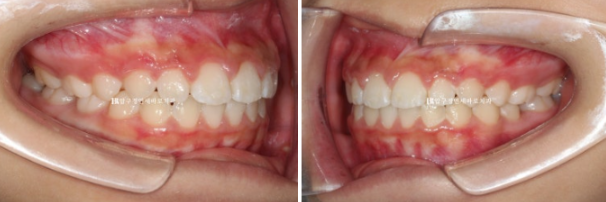

파란 화살표 측절치 치아는 아래와 거꾸로 물리는 반대교합입니다.

윗니 뻗침 즉 돌출 때문에 입술이 잘 안 다물어지는 입술부전증의 결과로 턱끝 근육이 울퉁불퉁하게 주름이 잡히는 호두턱 호두주름도 있습니다.

24년 4월까지 6개월간 장치를 낀 후 모습입니다.

24.04

중심선은 잘 맞고

영구치들이 잘 내려오고 있습니다.

앞니 뻗친 부분도 개선이 되었습니다.